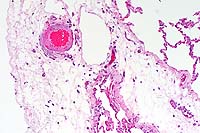

- Case 5- 2. Lung. Attached to the wall of this

pulmonary artery there are 3 endothelial syncytial cells. A 40x

objective view illustrates an eosinophilic intracytoplasmic inclusion

body separating the several of the nuclei of this cell.

- Case 5- 2. Kidney. Note the syncytial endothelial

cell expanding the wall of a small arteriole adjacent to the

glomerulus.

- Conference Note: In some sections of lung and kidney,

rare eosinophilic intracytoplasmic inclusions are present within

endothelial syncytia. Mild degenerative changes of glomeruli

and tubular dilatation were also noted by some conference participants.